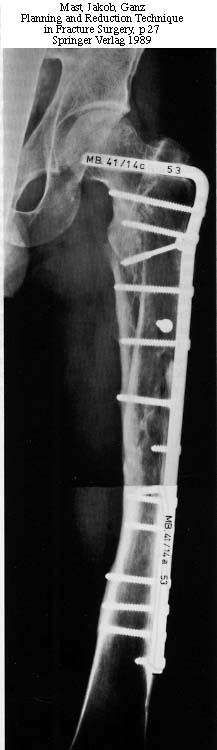

AP Pelvis

Lt femur

Rt femur

Lt hip

Rt hip

Lt leg incisions

We decided to fix the Lt femur with a few lag screws on the proximal part andstabilize the femur with long Richard plate that was inserted in a sub-muscularfashion, in order to avoid opening the main shaft fx (the so-called biologicfixation - see Lt leg incisions.).

On the Rt side I replaced the recon nail with a longer one (accepting its toolateral and anterior entering point), I added a proximal locking screw (anterior toposterior) in the subtrochanteric region through a self-made extra hole, and two 6.5cancellous hip screws posterior to the nail.